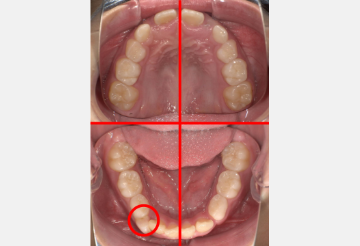

切歯(前歯)のうち少なくとも2歯が2/3以上萌出している

切歯は前歯のことです。インビザラインファーストは、2本以上の切歯が2/3以上生えていることが適用条件となります。

3/4顎に乳歯または未萌出の永久歯が2本以上ある

インビザラインファーストは、まだ生えてきていない乳歯もしくは永久歯が2本以上ある場合に適応となります。

3/4顎に乳歯または未萌出の永久歯が2本以上ない場合でも、上下左右3ヶ所の乳犬歯と第1乳臼歯・第2乳臼歯がそれぞれ2本以上乳歯である場合には適応となります。

永久歯を抜歯せずに矯正できる可能性が高い

インビザラインファーストでは、歯列弓(歯のアーチ)を拡張できることから、永久歯がおさまるスペースを作っておくことが可能です。そのため永久歯に生え変わった後、抜歯せずに矯正できる可能性が高まります。